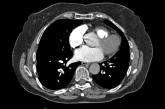

A computed tomography pulmonary angiogram

75-year-old woman • right-side rib pain • radiating shoulder pain • history of hypertension & hypercholesterolemia • Dx?